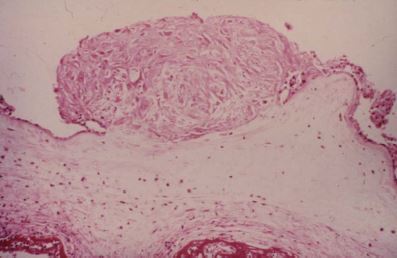

This pediatric liver tumor shows poorly differentiated spindle cells. What is the tumor and what is its unique staining pattern?

**Undifferentiated Embryonal sarcoma (UES)** IHC:  Desmin +  MSA +  Actin +  CK +  Myoglobin -  Vimentin, alpha-1-antitrypsin and alpha-1- antichymotrypsin +